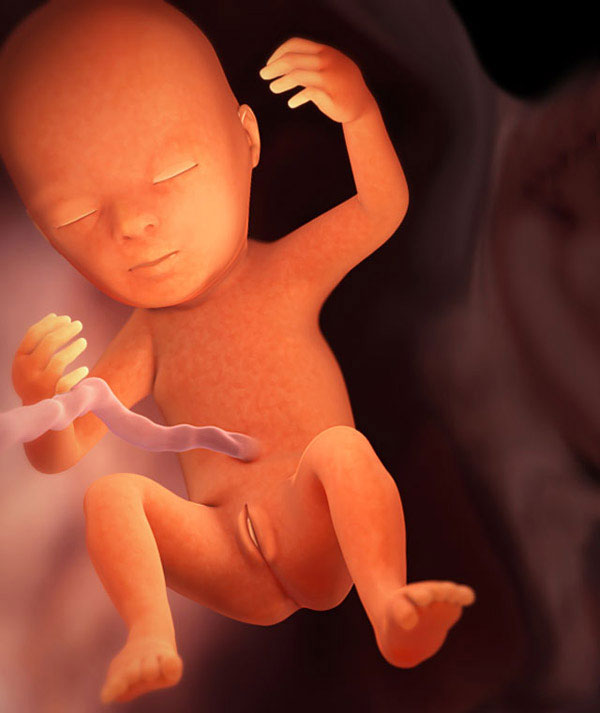

La 18e semaine de grossesse est de 4,5 mois lunaires. Le fœtus atteint 12,5-14 cm, pèse environ 150 g, il a les débuts des molaires. Si le bébé ne pousse toujours pas, il est sur le point de commencer. Une question importante - un garçon ou une fille va-t-il naître? - peut également devenir clair dans les prochains jours. Il est temps pour la future maman d'apprendre et de maîtriser les exercices de Kegel.

Qu'arrive-t-il au bébé

Le fruit croît rapidement. Ouvrez la paume de votre main. Maintenant, votre bébé s'y adapterait. Et voici comment évolue votre enfant:

la minéralisation du squelette continue, tous les os sont renforcés;- les muscles se développent;

- une couche de graisse sous-cutanée se forme;

- de minuscules articulations sur les doigts et les orteils se développent;

- le fœtus «s'entraîne» souvent, fait des mouvements réflexes (suce un doigt, se retourne, imite la respiration et avale le liquide amniotique);

- Au-dessus des petits rudiments des dents de lait, des embryons indigènes apparaissent - plus d'une douzaine d'années peuvent s'écouler avant que certains d'entre eux n'éclatent!